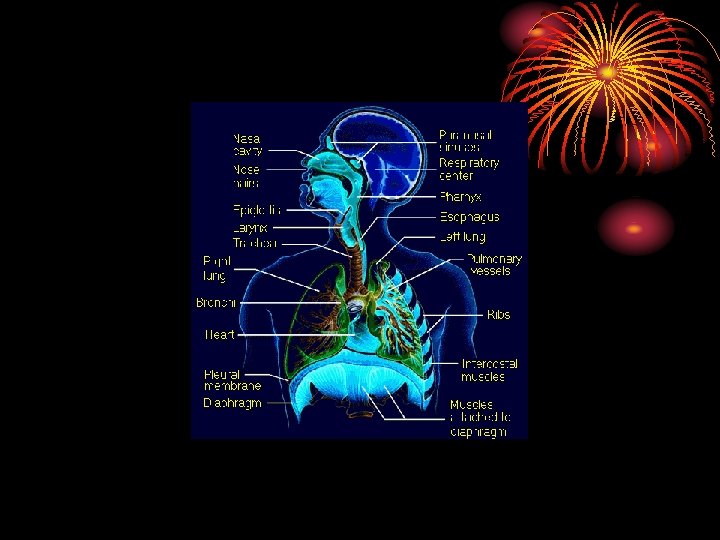

ANATOMY • Right lung three lobes and left two. • Each lobe divided into segments. • Trachea divides into main two bronchi then bronchioles, terminal b. and respiratory b. reaching the alveolar ducts to the alveoli. • Between the trachea and the alveoli airways divide 23 times, 16 conducting & 7 from resp. b. involved in gas exchange.

• area from 2. 5 cm 2 (trachea) to 11800 cm 2 in alveoli ? Air velocity. • 300 million alveoli, 70 m 2. • Alveoli lined by type 1 cells ( flat lining ) and type 11 cells ( granular pneumocytes secrete surfuctant ). • Pleura. • Respiratory muscles.